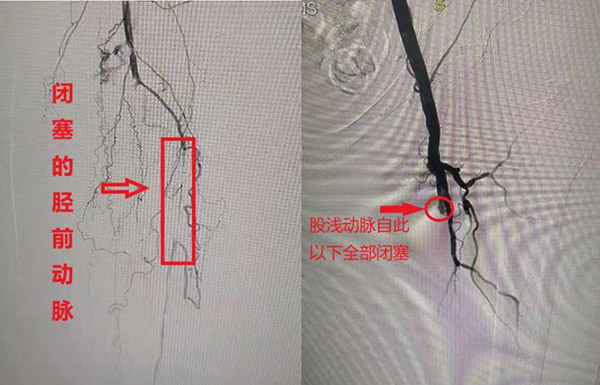

下肢CTA诊断验证了马轶的推测:老人双下肢都出现了严重的动脉闭塞。“血管有一个比较长的闭塞段,你看不到有血液从其中流过去,都是从边上侧支循环流过去的”,马轶说。

以 高奶奶的左腿为例,由于左股浅动脉和左胫前动脉均有大段闭塞,血液不能从腿上的主动脉顺利流过,只能由周边的血管代偿。然而周边的血管很细,根本达不到流 量和流速,所以造成了行走时的疼痛和跛脚。如果不立即进行治疗,下肢缺血会越来越严重,叠加上老人的糖尿病足,还可能演变成肢端坏疽,最终的结果就是截 肢。

图为术前左腿动脉造影 局麻之后,马轶开始为老人行左下肢动脉造影、球囊扩张术。导丝与导管交替配合,从斑块之间的缝隙蛇形前行。膝盖上端股浅动脉开通之后,马轶乘胜追击,左膝盖下端胫前动脉的短段狭窄也被开通。 历经四个小时,手术完美结束。造影显示,左腿五十多厘米长的闭塞段已经开通,血液沿着动脉血管直接流过——手术立竿见影。 图为术后左腿动脉造影 术后,马轶第二天一大早就去查房。还没等踏进病房,就听见高奶奶喊“马主任太厉害了,我这做过手术的左脚,明显比右脚热乎”。马轶向高奶奶解释,左侧足温明 显比右侧高,是因为介入术后原本堵住的血管被开通,左侧的末梢循环明显好于右侧。老人的儿子说,“咱看不懂啥造影,就知道我妈的脚好几年都没这么热乎过 了,马主任就是妙手”。道别之后,马轶刚要踏出病房,高奶奶又是一嗓子,“马主任啊,过一阵你还得把我右脚给整热乎了!”病房里一片欢笑。 温馨提示 预防动脉闭塞,根本上是要预防动脉硬化。长期的糖尿病患者、高血压患者,血管承受较高张力,相比于常人更容易出现动脉硬化,严重将导致动脉闭塞。一些青年人也出现这类问题,比如大动脉炎,多与长期的大量吸烟有关。